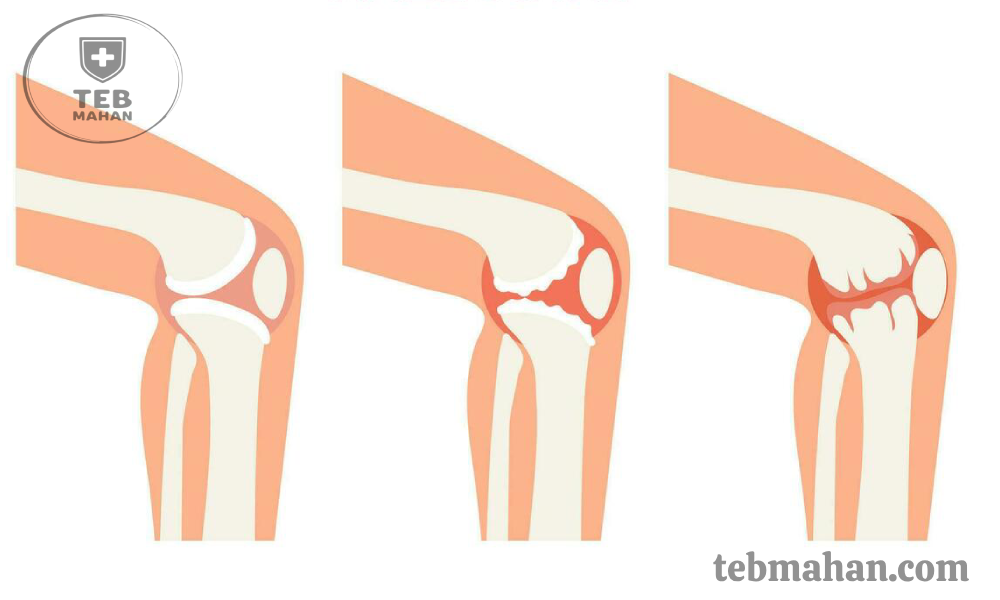

آرتروز زانو یکی از شایعترین بیماریهای مفصلی در جهان است، اما آنچه کمتر به آن توجه میشود این است که زنان بیش از مردان در معرض ابتلا به آرتروز زانو قرار دارند. تغییرات هورمونی پس از یائسگی، بارداری، آناتومی متفاوت مفصل و حتی انتخاب کفشهای نامناسب (مانند پاشنهبلند) از عواملی هستند که خطر بروز این بیماری را در خانمها افزایش میدهند.

آرتروز زانو نهتنها با علائمی مثل درد، خشکی و تورم حرکت را دشوار میکند، بلکه در صورت بیتوجهی میتواند کیفیت زندگی روزمره را تحت تأثیر قرار دهد. در این مقاله، بهطور ویژه به علائم آرتروز زانو در زنان پرداخته و سپس راهکارهای علمی برای پیشگیری و درمان آن را بررسی میکنیم تا زنان در هر سنی بتوانند با آگاهی بیشتر از مفاصل خود مراقبت کنند. برای آشنایی کاملتر با ماهیت این بیماری، علائم و علل آن، پیشنهاد میکنیم مقاله آرتروز زانو چیست را نیز مطالعه کنید.

در مراحل پیشرفته، آرتروز میتواند ظاهر زانو را تغییر دهد. انحرافهایی مثل پای پرانتزی یا پای ضربدری در زنان مبتلا دیده میشود که فشار بیشتری روی مفصل ایجاد میکند.